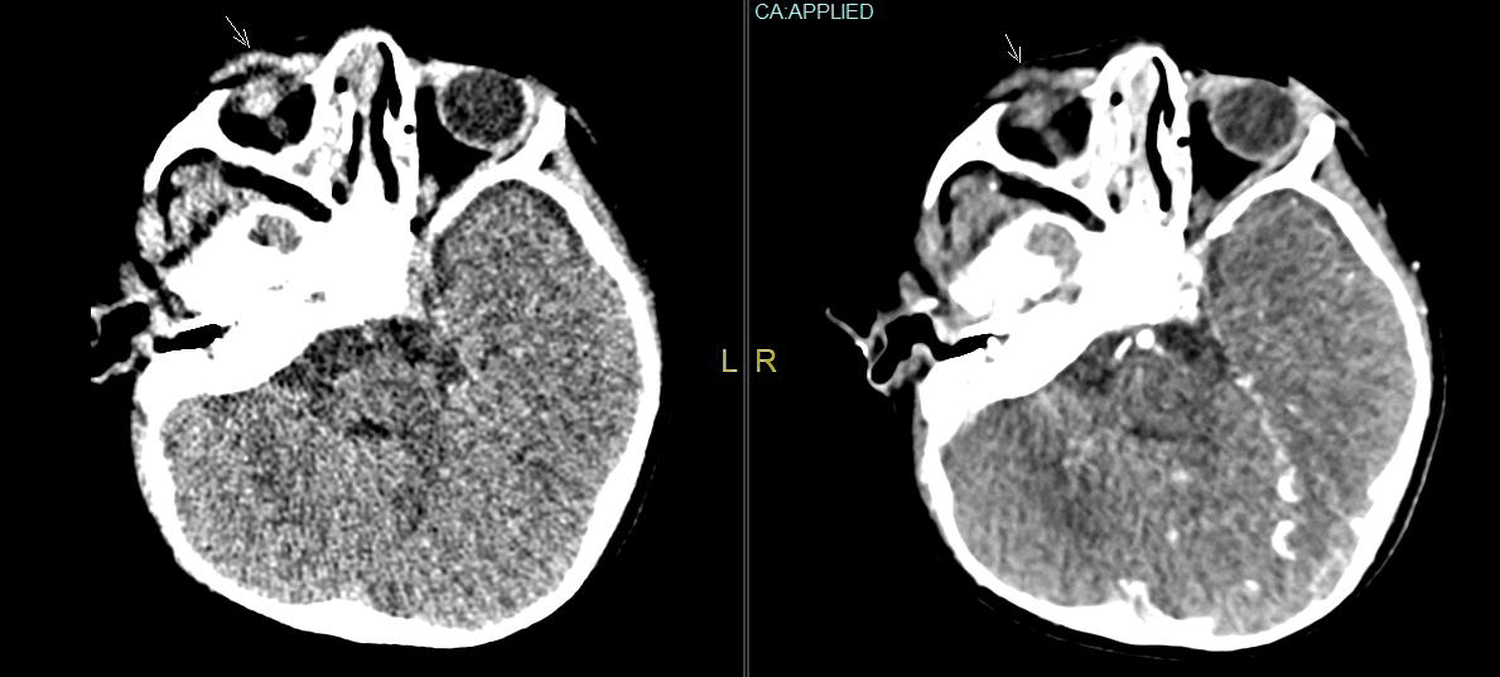

Unilateral Moyamoya Disease in an Adolescent Female of Non-Asian Descent: A Case Report

Aaron Peterson, BS, Trinity Puno, BS, Joshua Levy, MD, Angus Cheng, DO, Jabre Millon, MD, Tim Stone, MD, Isaac Wang, DO, Rajpaul Gill, MD, Millie Pal, DO, Kyle Mefferd, PhD, Denise Vidal , MPH, Angelina Rodriguez, MD, Upinder Singh, MD

1-7